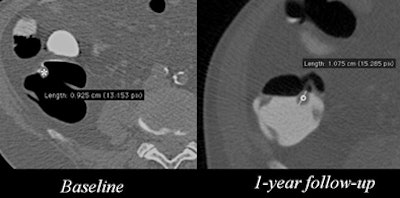

| Patient had a subcentimeter polyp in the ascending colon that grew to more than 1 cm after one year. Image courtesy of Dr. Lorenzo Faggioni. |